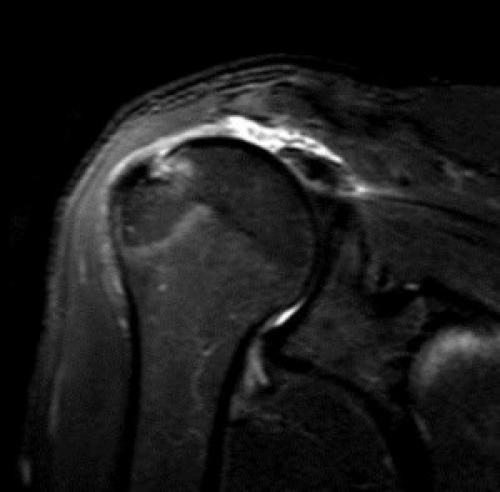

Повреждения плечевого сустава встречаются относительно часто. Причинами служат чрезмерный объём движений в суставе или падение на вытянутую руку. Встречается также нетравматическая этиология нестабильности при заболеваниях соединительной ткани. МРТ плечевого сустава наряду с его рентгенографией являются главными методами выявления травмы.

Наиболее типичным (около 85% передних смещений травматической этиологии) является повреждение Банкарта – отрыв фиброзного или фибрознохрящевого фрагмента от края суставной впадины в месте прикрепления связки к суставной впадине с повреждением суставной губы. Кроме того, травма может приводить и к костным повреждениям – перелому гленоидного кольца спереди, костному повреждению Банкарта (то есть повреждению Банкарта в сочетании с переломом) и перелому большой бугристости.

МРТ плечевого сустава. Корональные Т1-взвешенные МРТ. Переломы Хилла-Сакса и Банкарта.